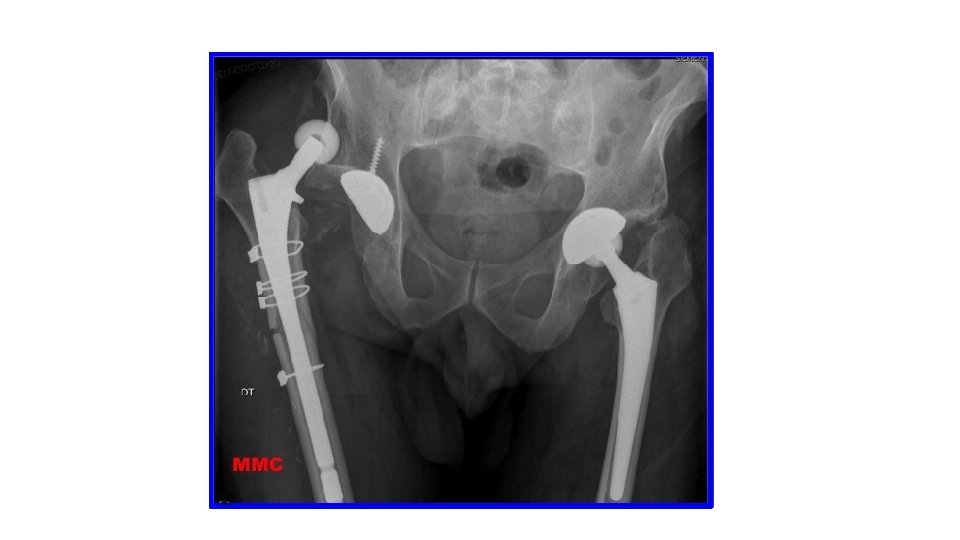

• Epaule • Coude • Patella • Hanche et PTH • Doigts •

• Epaule • Coude • Patella • Hanche et PTH • Doigts • Mâchoire • Tendon d’Achille